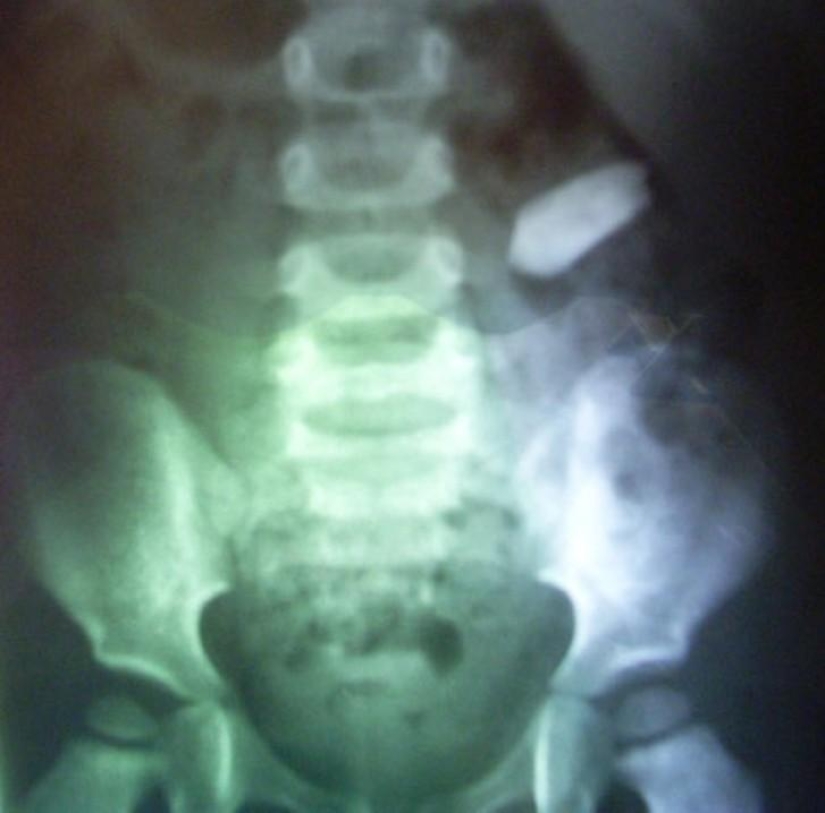

2. The bullet.